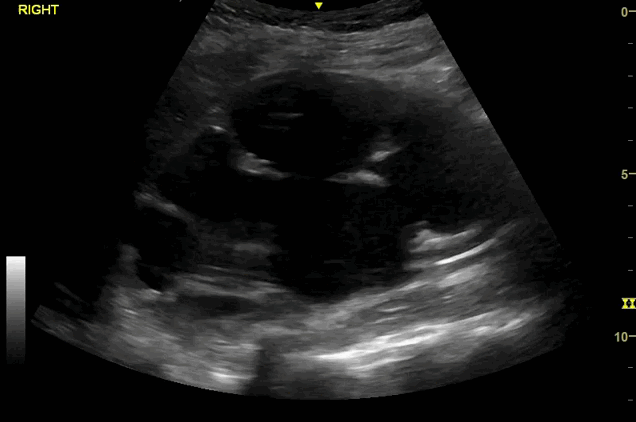

You decide to perform renal POCUS in ED as shown below: -

Clip 1- Longitudinal view right renal

• Bilateral hydronephrosis, worse on the right, with the right kidney measuring 128mm in length.

• Right side Grade IV (severe) hydronephrosis due to the obvious significant cortical thinning, left side Grade II-III (moderate)

• Comparing the POCUS images with the previous US KUB from a year ago, it shows a very significant increase in right kidney length, with evident of moderate to severe bilateral hydronephrosis.

In the context of fever and vomiting, this should raise alarm bells for obstructive infective nephropathy requiring urgent urological intervention.